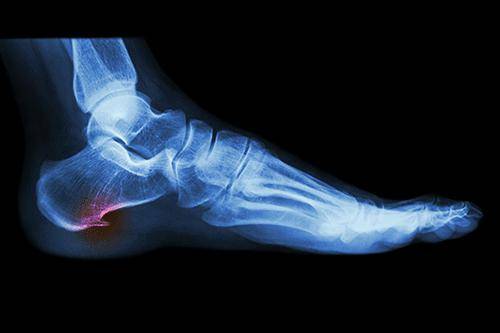

Как формируется пяточная шпора

Поскольку шпора на пятке (симптомы и лечение будут описаны ниже) не является самостоятельным заболеванием, никаких неприятных ощущений именно нарост не приносит. Причиной появления невыносимой боли является травматизация связок ступни. Причем повреждения могут одновременно образоваться на двух ногах. Помимо этого, следует знать, что на ступне имеется слизистая сумка, которая также может воспаляться и повреждаться. Пяточная кость реагирует на это так же, как и при артрозе, то есть начинает расширяться и приобретать форму нароста. Обнаружить недуг визуально практически невозможно, зато он очень хорошо просматривается с помощью рентгена.

Методы диагностики

Диагностика пяточной шпоры не представляет трудностей для специалиста. Как и чем лечить шпору на пятке, врач сможет установить, только выяснив причины заболевания, изучив симптоматику, выяснив точное ее место расположения, стадию и давность болезни.

Первое, что ожидает пациента на приеме, это клинический осмотр методом пальпации больной пятки. Этого метода иногда бывает вполне достаточно, особенно в более запущенных формах, когда нарост заметен визуально и легко пальпируется.

На ранних стадиях заболевания диагностика может быть несколько затруднительной. В таких случаях может быть целесообразно проведение дополнительных исследований. Речь идет о рентгенологическом исследовании области пятки.

Однако клиническая картина и присутствие воспалительного процесса остается основным аргументом для постановки диагноза.

Очень важно при обращении к специалисту правильно дифференцировать данную патологию от других с похожими клиническими проявлениями.

Так, исключить травмы пяточной кости, трещины и переломы, которым свойственны аналогичные болевые ощущения, можно с помощью рентгенологического сканирования. Дифференцировать шпору от заболеваний ревматического характера, при которых также имеет место воспалительный процесс мягких тканей, можно с помощью биохимического анализа крови пациента.

Диагноз ставится на основании жалоб больного, пальпации поврежденной конечности и рентгеновского снимка. Для выяснения причин воспалительного процесса могут потребоваться дополнительные исследования: общий анализ крови, биохимия, пункция из поврежденной области. Если принято решение лечить заболевание терапевтически, то следует полностью довериться врачу.